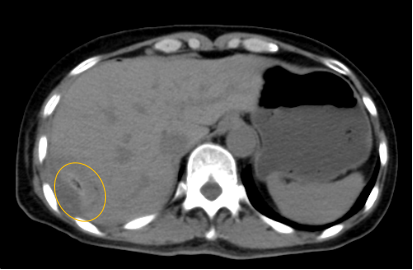

入院后,影像診療中心立即給李女士完善了CT和MR檢查,發(fā)現(xiàn)病變位于肝包膜下,臨近膈肌,消融治療過程中有并發(fā)損傷膈肌的可能,難度較大,但是采用精準(zhǔn)影像定位是可以完成的。陳寶瑩主任立即與腫瘤三病區(qū)劉金鵬主任聯(lián)系,并與影像微創(chuàng)治療小組進(jìn)行MDT討論:患者為卵巢癌肝右葉包膜下單發(fā)轉(zhuǎn)移瘤,最長徑不超過3cm,患者對局部治療的主觀愿望強(qiáng)烈,符合消融治療專家共識,遂制定了影像引導(dǎo)下局部消融治療聯(lián)合全身治療的綜合治療方案。

針對這個特殊部位的腫瘤,要想消融完全,那么膈肌損傷的風(fēng)險就很高,陳寶瑩主任帶領(lǐng)影像微創(chuàng)亞專業(yè)組成員仔細(xì)閱讀CT圖像,設(shè)計進(jìn)針路徑,結(jié)合MR圖像確定腫瘤活性范圍,制定了周密而詳盡的消融計劃。臘月二十九,即住院第二天影像微創(chuàng)治療小組圓滿為患者完成了腫瘤微波消融治療,觀察24小時后出院回家過年。術(shù)后48小時隨訪患者無明顯不適,術(shù)后7天隨訪,患者肝功、血常規(guī)等各項指標(biāo)均恢復(fù)正常。